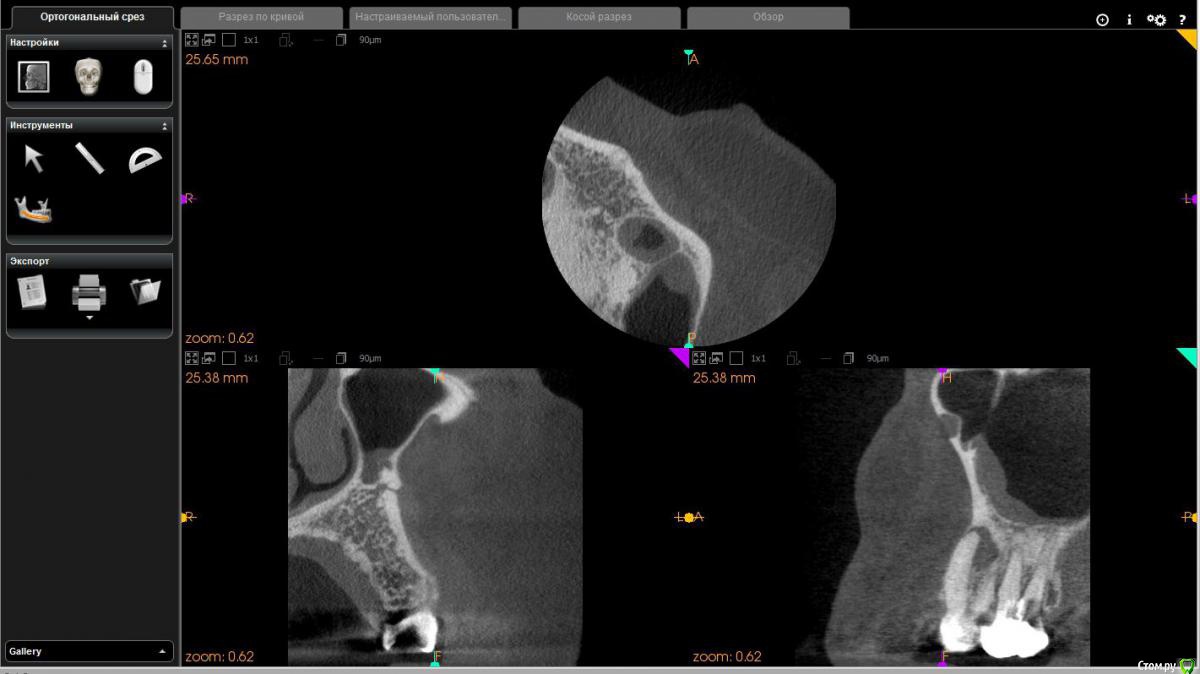

Диана135 Опубликовано 31 марта, 2017 Поделиться Опубликовано 31 марта, 2017 Здравствуйте! Год назад лечила зубы, осенью над одним из них появился флюс, который до сих пор не исчезает, это доставляет мне дискомфорт. Стоит ли продолжать лечение или проще удалить? Прилагаю описание КЛКТ: Зуб 2.6 коронковая часть восстановлена рентгеноконтрастным материалом. Трех корневой, четырёх канальный (в медиально-щечном 2 канала). В медиально-щечном корне каналы прослеживаются, в одном из каналов, в верхней трети определяются фрагменты рентгеноконтрастного материала. В небном корне в верхней трети рентгеноконтрастный материал. В средней трети корня определяется внутрикорневой очаг деструкции 2,2×3,7 мм с резорбцией дистального края и линией просветления от очага деструкции в медиальную сторону апикальной трети. В проекции медиально- и дистально-щечных корней определяется ограниченный очаг деструкции однородной структуры, с неровными контурами, с разрушением наружной кортикальной пластинки и распространением процесса в сторону корней 2.8 зуба. Кортикальная пластинка дна верхнечелюстного синуса в проекции деструкции истончена с набуханием слизистой до 4 мм.Зуб 2.7 Коронковая часть восстановлена рентгеноконтрастным материалом. Трех корневой, четырёх канальный (в медиально-щечном 2 канала). В каналах определяется рентгеноконтрастный пломбировочный материал: в медиально-щечном корне, один из каналов не обтурирован, другой не до верхушки, в дистально-щечном обтурация не до верхушки, в небном до апикального отверстия. В области верхушек медиально и дистально щечных корней определяется деструкция до средней трети длины корней, с расширением пространства периодонтальной связки.Отмечается общая горизонтальная убыль костной ткани до 3 мм. Ссылка на комментарий

Диана135 Опубликовано 1 апреля, 2017 Автор Поделиться Опубликовано 1 апреля, 2017 Скриншоты снимка. Ссылка на комментарий